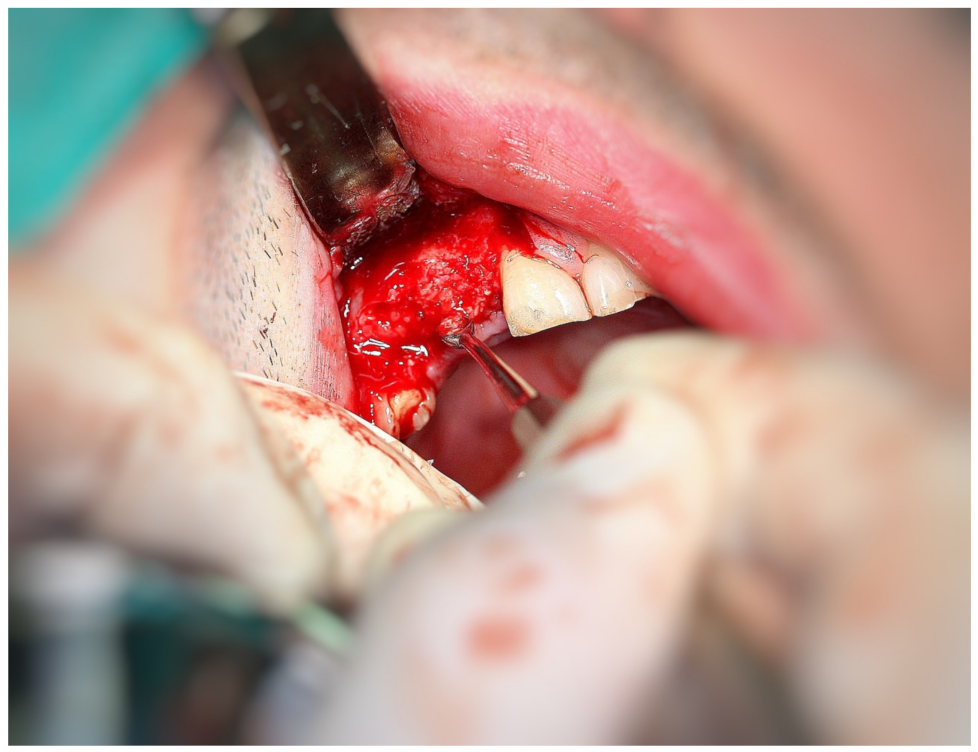

3.2. Surgery